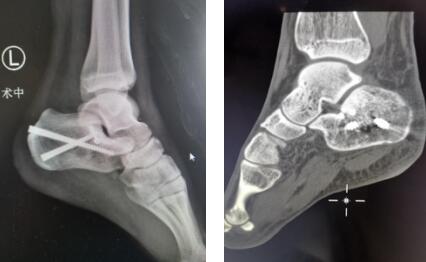

2.1左跟骨术前CT

2.2左跟骨术前规划

2.3内固定术后情况